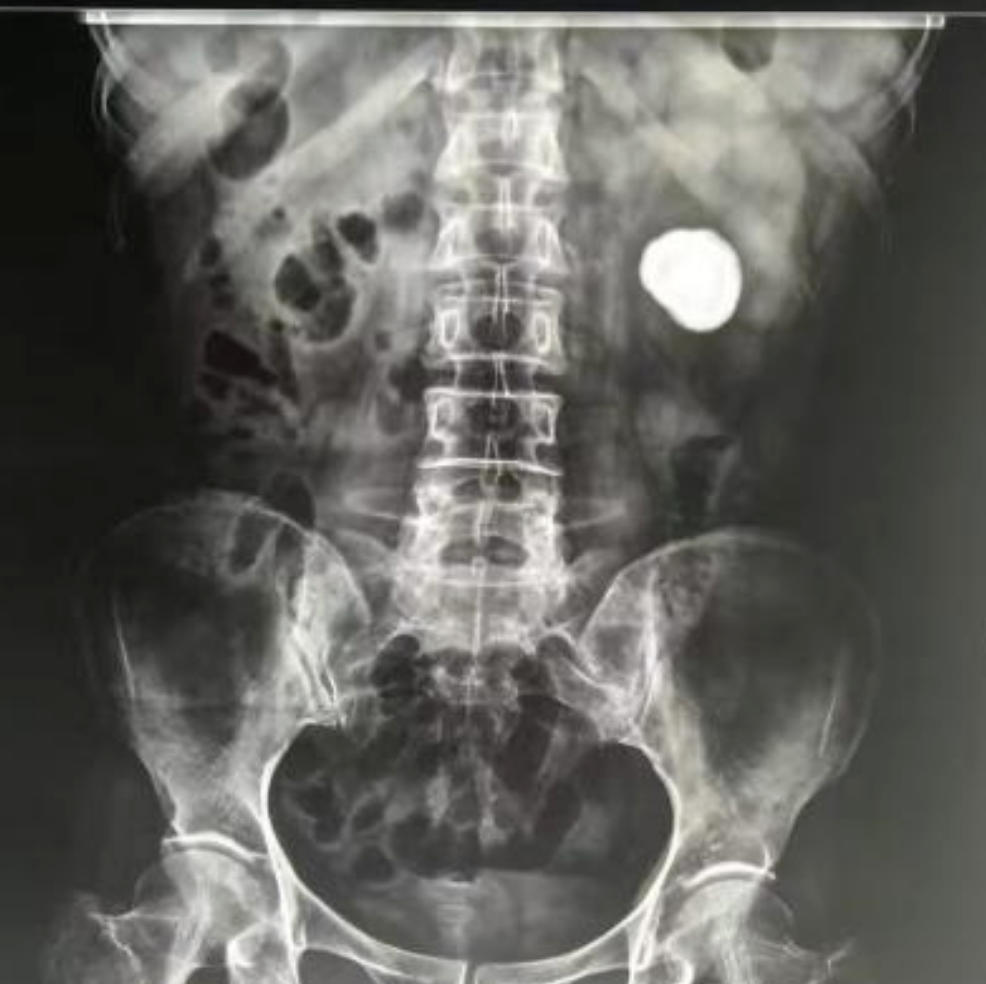

1.诊断方法:医生通常会结合症状,进行尿常规、B超、CT等检查来确诊结石的大小、位置和数量。